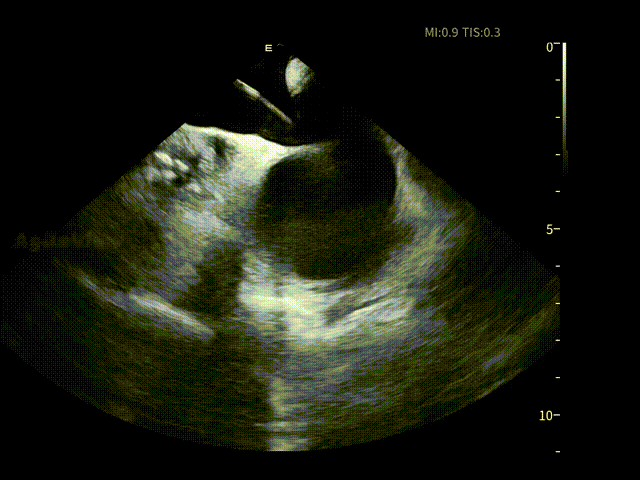

在完成房颤消融关键步骤后,薛枫教授操作7.5Fr AgileView™ ICE导管进入左心房,该导管为四向180°打弯,可轻松进入左房,为后续左心耳评估与封堵操作提供无缝衔接的影像支持。

通过ICE的多角度实时成像,术者在左房内近距离观察左心耳的开口形态、分叶数结构及周围解剖关系,并对潜在血栓进行动态筛查,并选择合适的封堵器型号选择并制定释放策略。

封堵器释放